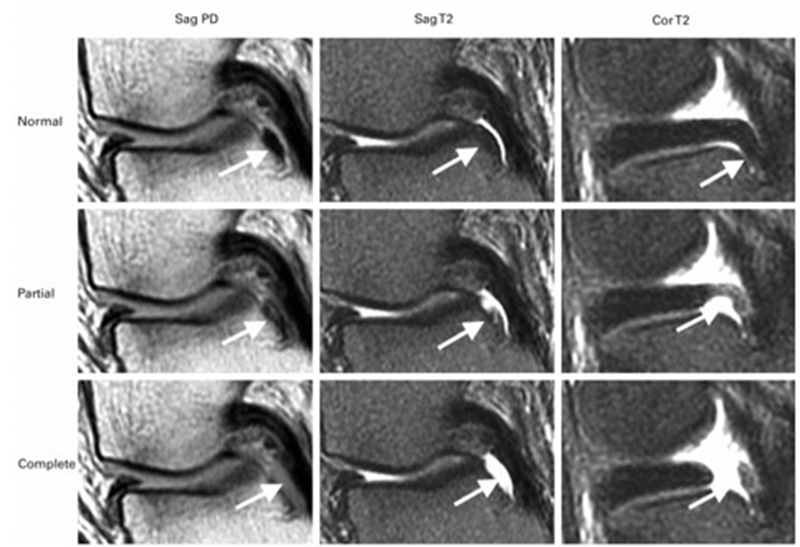

SONK与内侧半月板后根部损伤,有国外学者在SONK患者中通过MRI及关节镜检查,常可发现合并内侧半月板后根部的撕裂,该发生率可达到80%(24/30), 15例完全撕裂,9例部分撕裂。结果表明SONK可能与内侧半月板后根部撕裂后,导致股骨负重区的应力集中、软骨下骨髓水肿有关。

对于半月板损伤类型对SONK的影响,一项研究结果显示内侧半月板后根部撕裂组的半月板突出率为46.1%,平均坏死面积为423.1mm2。内侧半月板后角水平裂组的半月板突出率为35.3%,平均坏死面积为175.8mm2。

与内侧半月板后角水平撕裂相比,后根撕裂将导致更大程度的突出和更广泛的骨坏死。